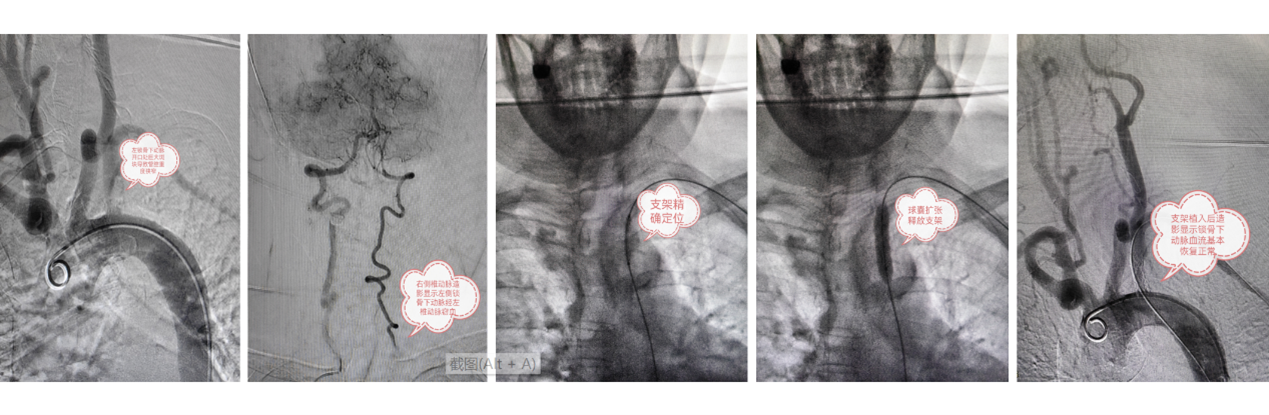

今年73岁的朱女士诊断了多年的高血压病史,平时头晕手麻,甚至好几次眼前出现黑蒙晕倒,严重影响日常生活,通过药物控制还是没有明显改善。经人介绍专程来心血管外科找到相里伟医生,经简单查体发现双上肢血压相差高达90mmHg,左桡动脉搏动无法触及。进一步颈部血管超声和颈动脉CTA检查后发现左锁骨下动脉重度狭窄,症状体征和影像学检查都不支持单纯的高血压诊断,而是符合左锁骨下动脉盗血综合征。心血管外科裴斐主任指导下,由介入团队相里伟和张忆雯医生仔细术前评估后,在张明医生配合下先完成冠状动脉造影排除冠心病,再选择适当导丝正向通过狭窄段血管建立治疗通路,根据球扩覆膜支架定位准确的特点在病变段精准植入新型的LifeStream支架(图1)。术中左上肢脉搏即刻恢复正常。术后双侧上肢血压对称,复查超声显示左锁骨下动脉支架形态良好,管腔接近正常血流通畅。这也是新型球扩覆膜支架治疗外周动脉狭窄病变在我院的首例应用。患者术后12小时下床,3天出院,术后四周随访恢复情况良好,以往不适症状完全消失。

图1.